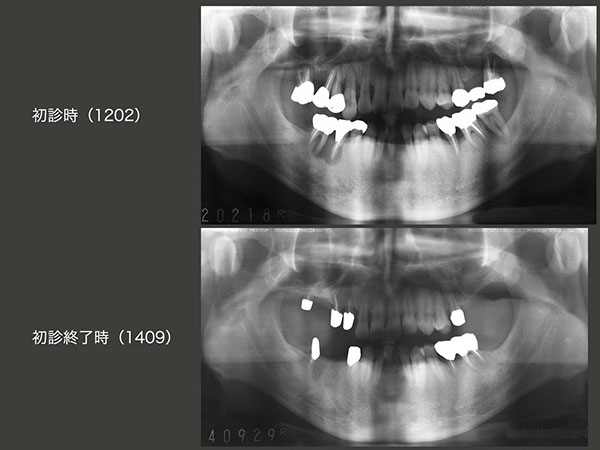

初診時および初診終了時のパノラマX線写真の比較.保存不可能な歯の抜去を4本,ヘミセクションを2本行った.自然挺出を行った右上3および左下5の歯周ポケットが改善したことから,本来人間の持つ自然治癒力の高さに驚かされた.